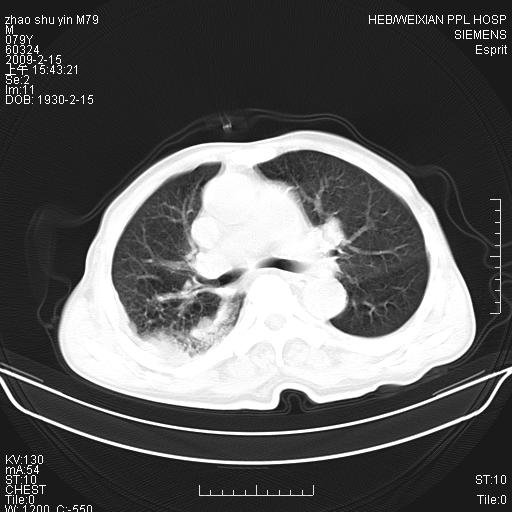

标题: CT18303:M79Y,右下肺病变

主因高热、寒战4天,伴有咳嗽,腹痛。

1。右下肺磨玻璃及蜂窝影考虑炎症 建议抗炎治疗后复查

2。右侧胸膜增厚 、右侧包裹性积液

3。心影增大 ,左心房增大为甚

4。右下肺门饱满(肿大淋巴结)

右下肺蜂窝影加右下肺门淋巴结肿大,要考虑肺泡癌。

我考虑:1、右下肺肺泡癌并感染,肺门淋巴结转移可能性大。2、右侧胸腔积液。